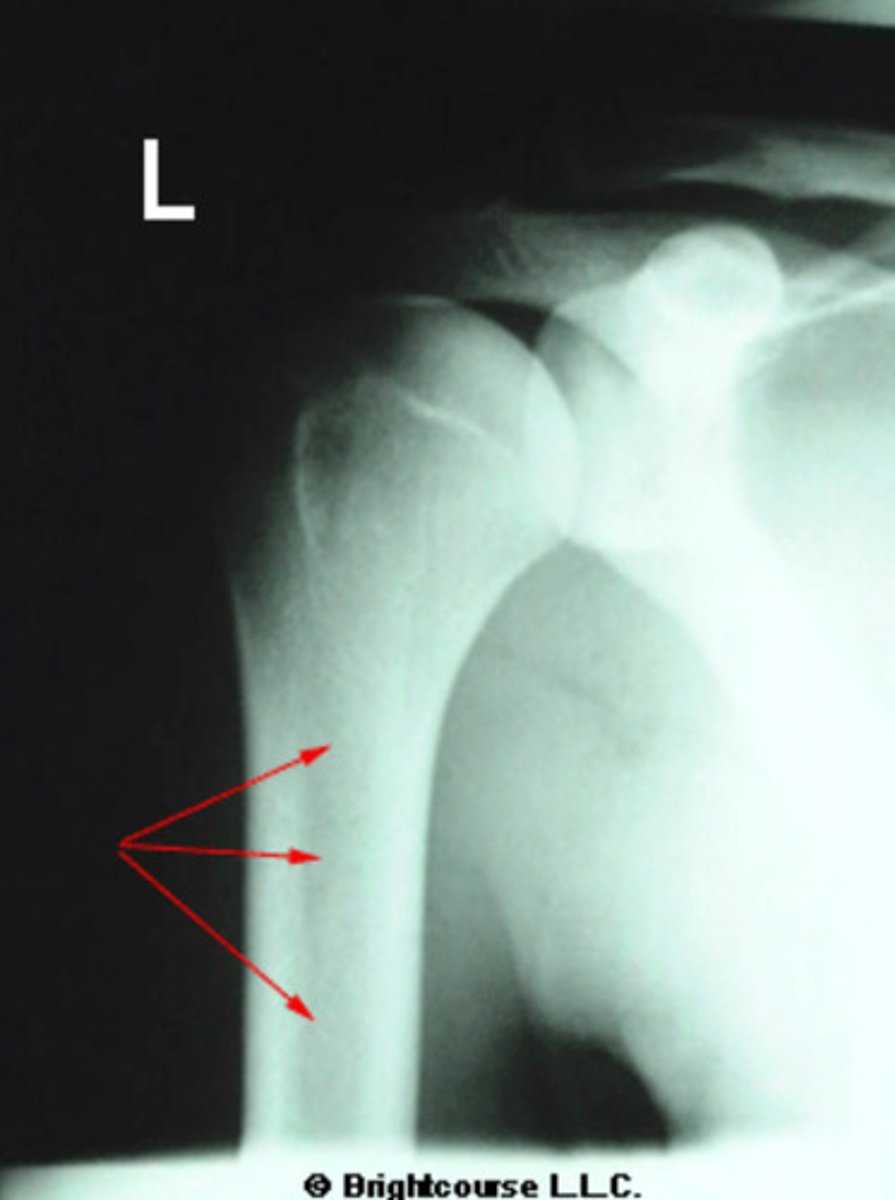

Soft tissue

What is being pointed out by the arrows in this image?

Proximal shaft of humerus

What is being pointed out by the arrows in the image?